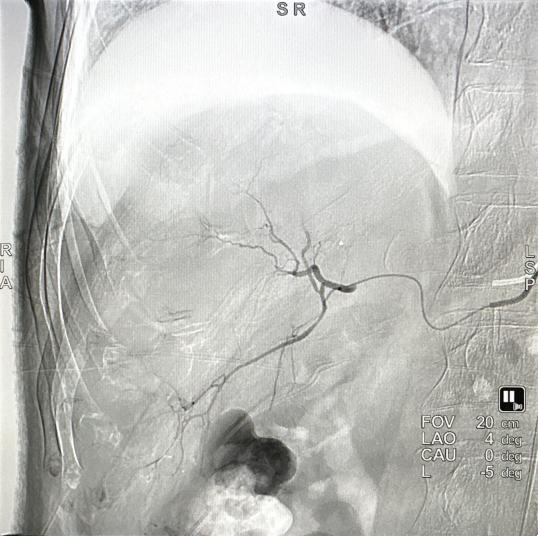

一切准备就绪,放射科主任罗谞成协助朱晖教授进行介入手术。穿刺点局麻后,朱晖教授在B超引导下穿刺插管,在DSA设备的帮助下,对肝右及肝中动脉较纤细、远段分支位置的六处结节进行精准打击。术中,朱晖教授把导管送进肝肿瘤的供血动脉中对其进行栓塞,阻断其血供,使肿瘤趋于坏死,并向病灶集中释放药物。手术非常顺利,历时仅2小时。由于患者血小板较低,为防止血肿的发生,朱晖教授亲自按压止血30分钟,确定穿刺处无出血、无血肿后,再进行加压包扎。最后安全护送患者至病房,并进行了详细的术后指导。患者及家属不胜感激:“这趟求医之路实在是太值得了,朱教授又救了我一命,谢谢你们!”这是患者的肺腑之言,也是医患间最动人的情谊。

术后造影